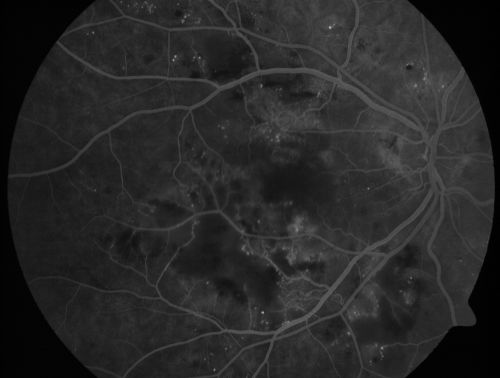

Diabetic Patient with Macular Edema and Blood Pressure 200/95

49-year-old decreasing vision over the last year. OD is 20/80, OS 20/80. blood pressure which was 200/95.

Hypertensive Retinopathy in a Diabetic

macular edema

cotton wool spots

diabetic

hypertensive